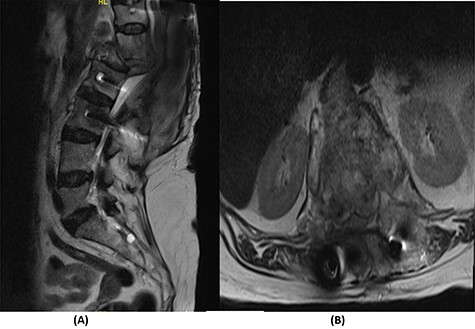

Over a year after the surgical procedure with the bridging technique, the patient presented with a new-onset lower back pain after hearing a crack. X-ray showed bilateral rod fractures and the CT scan showed re-ossification of the involved levels (T11–L3; Fig. 5). An MRI showed complete recovery of the infection without cord compression (Fig. 6). At this stage, we elected to proceed with a revised surgical intervention that involved adding bilateral pedicle screws at the re-ossified vertebrae (T11, T12, L2 and L3). The patient tolerated the surgery well and had a normal neurological examination postoperatively. CT scan post revision demonstrated fixation of T5 to S2 alar-iliac with a well-fixed construct. CRP level upon discharge was 7 mg/l and procalcitonin was <0.02 ng/ml. The patient was recovering well at follow up 1 year later (Fig. 7).

(A) T2-weighted sagittal spine MRI demonstrating changes at the thoracolumbar spine with complete resolution of infection and no cord compression. (B) T2-weighted axial spine MRI of the corresponding level of L1 vertebral body.